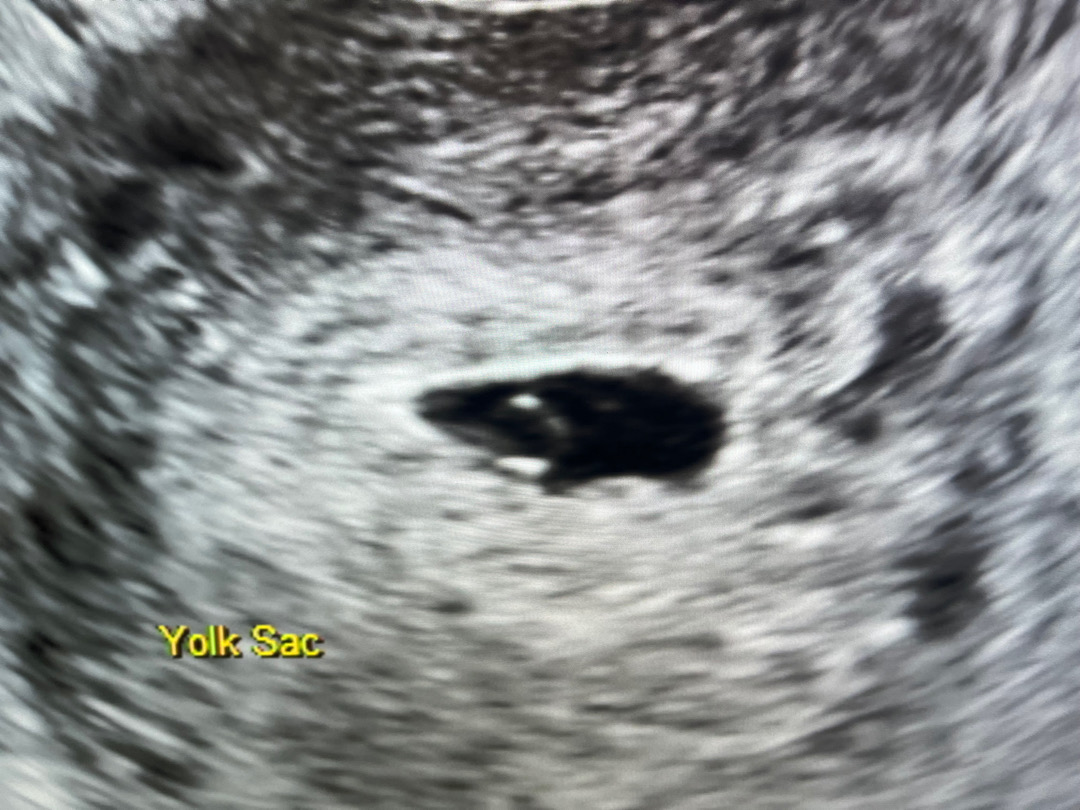

5주4일차

5주4일차 초음파입니다 난황까지만 보이고 아기는 아직 안보이는거죠?

저도 저정도였어요! 아기 모습 정도는 7주 되어야 보인대요